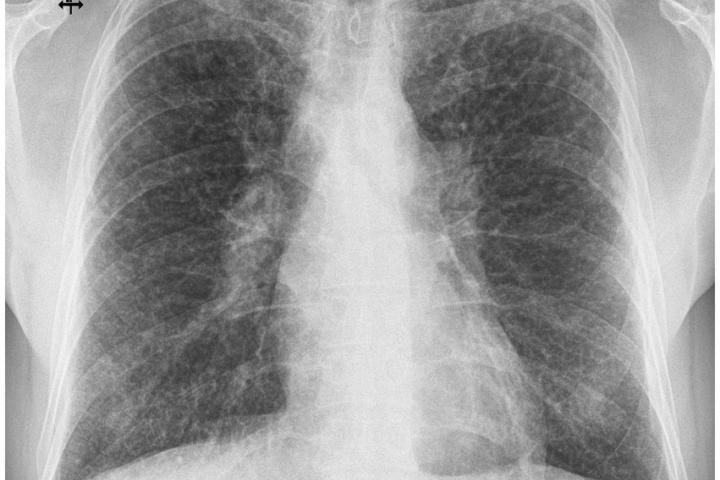

Sarcoidosis is a systemic inflammatory disease which is characterised by the formation of granulomas, clusters of immune cells, which most commonly affect the human lungs. Despite decades of research, there is still no single, definitive diagnostic test for Sarcoidosis. In practice doctors rely on the process of exclusion, first ruling out other conditions which have overlapping features, particularly TB, a widespread infectious disease caused by Mycobacterium tuberculosis (M.tb).

Due to the biological similarities between these two conditions,  the research team set out to study whether immune responses specific to M.tb could be used to reliably distinguish Sarcoidosis from active TB disease. In this study research team hypothesised that immune “signatures” triggered by M.tb antigens would differ between patients with Sarcoidosis and those with TB.